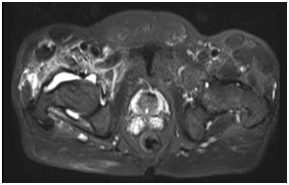

Intraoperative specimen culture, again grew the same previous pathogen. Repeated blood culture prior to discharged was with no growth. The patient was treated with an 8-week regimen: including 6 weeks of intravenous Ceftriaxone followed by 2 weeks of oral Levofloxacin, despite appropriate management. However, the patient continued to have severe pain in the right hip along with severe motion restriction. Two months later, MRI of the right hip with intravenous contrast was preformed and it showed worsening of the osteomyelitis and septic arthritis of the right pelvis, right femoral head/neck region. (Figure 2).